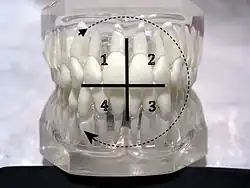

Le système de normalisation ISO de repérage des dents chez l'être humain, proposé par l'Organisation mondiale de la santé (OMS), est largement utilisé par les professionnels de la santé dentaire. Il est basé sur le système de notation utilisé par la Fédération dentaire internationale (FDI) et est connu sous le nom de ISO 3950[2].

Dans ce système, la dentition humaine est repéré selon quatre quadrants divisant les deux mâchoires. Dans chaque quadrant, les dents sont numérotés de 1 à 8.

Le quadrant est lui-même indiqué par un numéro de 1 à 8, selon sa position et selon le type de dentition décrit (provisoire alias « dents de lait » ou définitive alias « dents d'adulte »).

Le repérage « gauche » - « droite » fait référence à la position dans la bouche du patient mais correspond à la vision du dentiste ; la gauche et la droite sont donc inversées.

|

Dentition permanente

(« dents d'adulte »)

supérieure droite - 1 supérieure gauche - 2

18 17 16 15 14 13 12 11 | 21 22 23 24 25 26 27 28

DROITE --------------------------------------------------- GAUCHE

48 47 46 45 44 43 42 41 | 31 32 33 34 35 36 37 38

inférieure droite - 4 inférieure gauche - 3